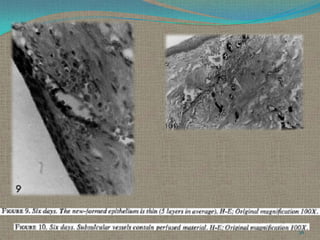

Six Days.

The epithelium already covers the cut surface of the connective tissue. It is very

thin, being formed by an average of five layers of flat epithelial cells. The

connective tissue is healed and there is no

apparent inflammatory infiltrate. A large

number of loaded small capillaries is present

directly beneath the sulcular epithelium.

At the cemento-enamel junction the bottom of

the long epithelial attachment and the insertion

of Group III fibers can be seen forming a well

collagenated area. Group I is still disorganized..